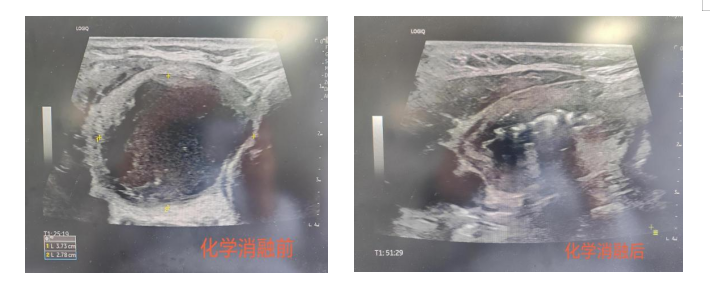

化學消融術案例:首例化學消融術患者為62歲男性,因頸部腫脹、吞咽伴異物感明顯就診,超聲檢查顯示其甲狀腺右葉存在直徑約4cm的囊性為主混合性腫物,已對氣管造成明顯壓迫。傳統手術需切除部分腺體,存在神經損傷及終身服藥風險。經多學科討論,團隊決定采用化學消融術:在超聲引導下,將硬化劑精準注入囊腔,通過化學作用使囊壁內皮細胞失活,促進囊液吸收。術后24小時,患者壓迫癥狀顯著緩解,復查顯示囊腔體積縮小60%以上。